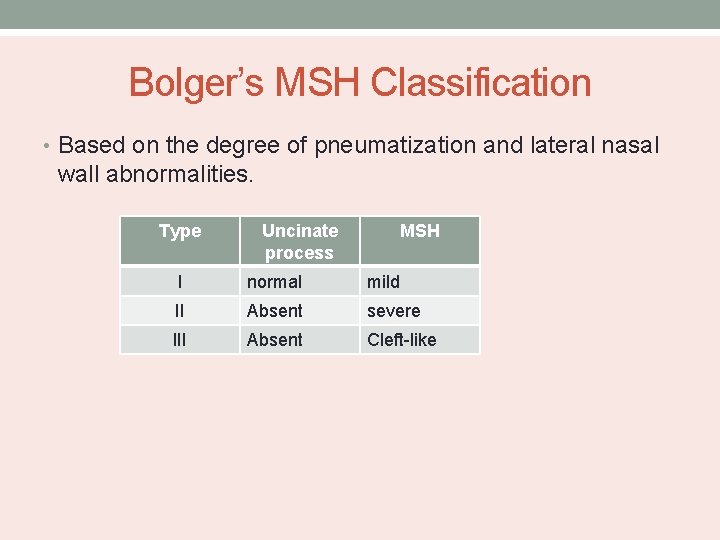

Bolger’s MSH Classification • Based on the degree of pneumatization and lateral nasal wall abnormalities. Type Uncinate process MSH I normal mild II Absent severe III Absent Cleft-like